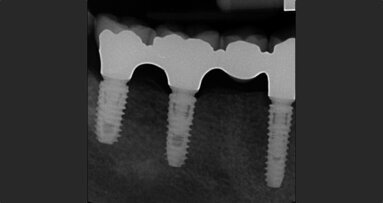

Objective: The objective of this study was to evaluate the implant survival and success rates as well as the physiological marginal bone remodeling expected...

The long-term clinical success of dental implants is dependent upon osseointegration, which is defined as a direct functional and structural connection ...